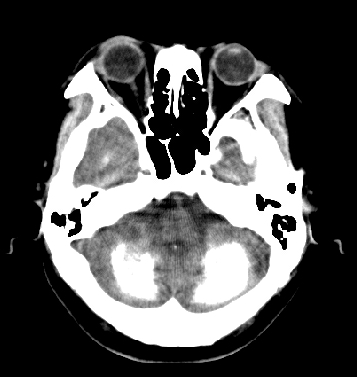

女性 38岁 病人脚弓反张 8岁以后不能行走 今年查pth11.9ng/ml(正常28ng/ml)

这么弥漫的钙化还第一次见。

考虑甲状旁腺功能减退症,该病是因甲状旁腺激素分泌减少或功能障碍所引起的少见病。其特点是低血钙,高血磷,且血pth极低。因低钙常可引起神经精神激惹症状,包括手指,趾,口角麻木,严重时可出现肌肉痉挛,喉哮鸣和惊厥,甚至癫痫样发作,有的可出现抑郁症及精神失常。长期的高磷血症可引起脑内结构对称性多发性钙化,特别是小脑和基底节的钙化可致锥体外系症状,而钙化的ct表现为类似于脑出血的密度增高影。

原发性甲状旁腺功能减退症和fahr病都有神志上的改变等症状,且头颅ct检查均可见颅内出现钙化。但fahr病无pth低下,ct表现钙化影在大脑半卵圆中心皮髓质交界处、丘脑、小脑齿状核等处。 而甲状旁腺功能减退症pth极低,ct虽可见钙化影,但部位在小脑和基底节等处。